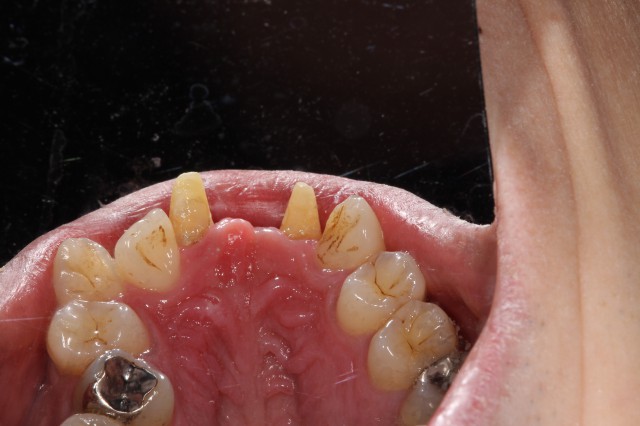

セラミックブリッジ施術例2(咬合面観)

施術前

前歯の欠損をセラミックブリッジで補綴治療した施術例です。(咬合面観)